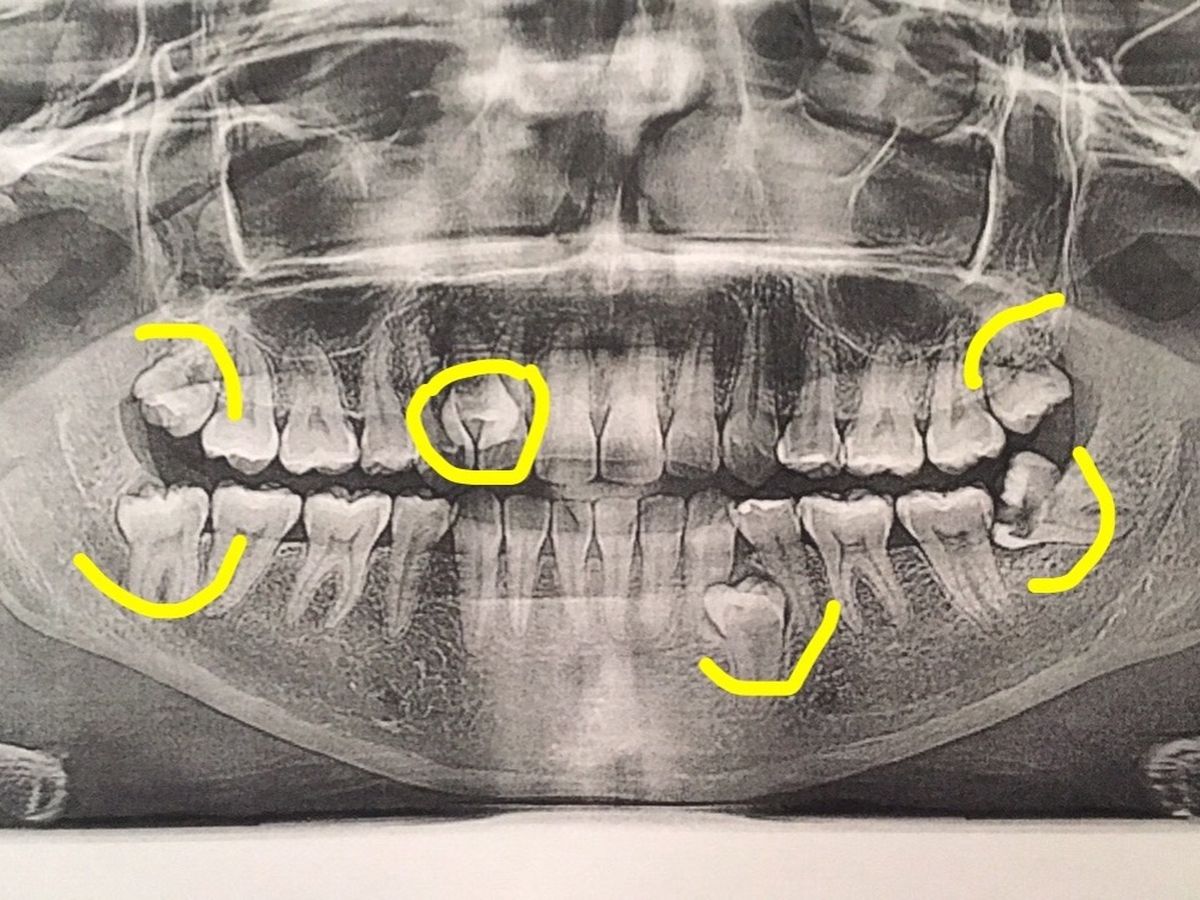

I have 4 wisdom teeth coming, one of them  coming in completely sideways that now has a hole in it, and is close to hitting my jaw bone that needs to be out urgently. It has been causing pain, fogginess, and migraines.

In addition to that, I have 2 extra (supenumerary) teeth, one that is already out, and the other on the same side as the impacted wisdom tooth, creating pain and discomfort as well.